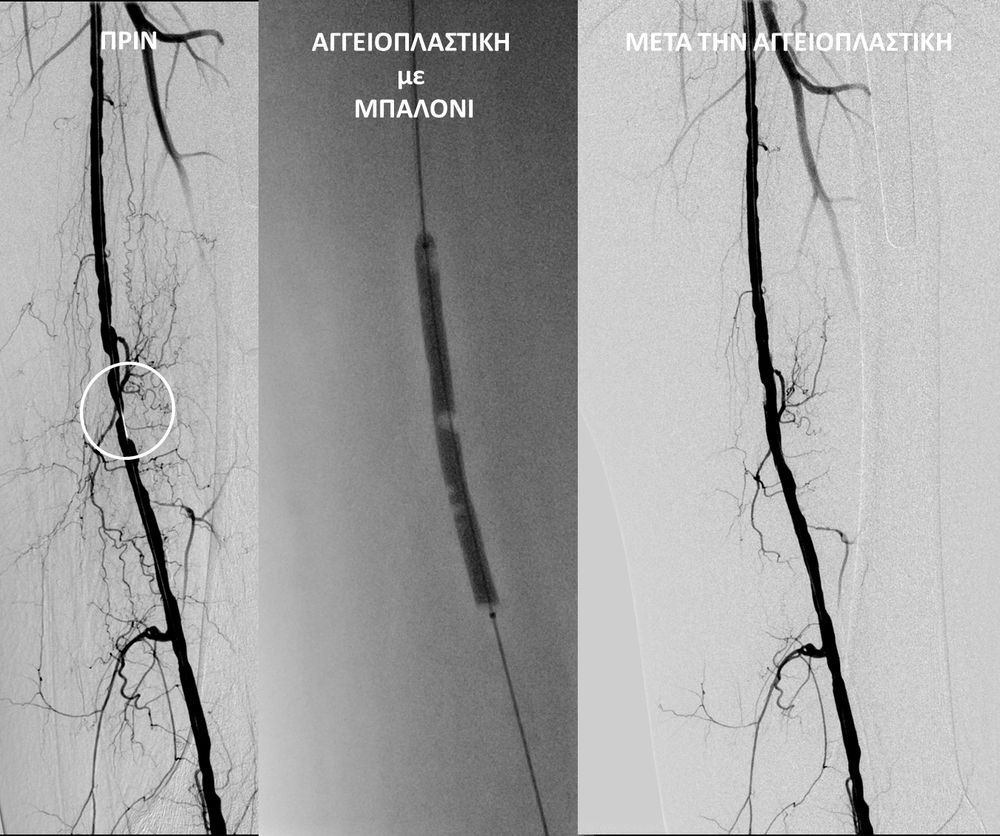

• Η αγγειοπλαστική των αρτηριών είναι μία μη χειρουργική επέμβαση που αποσκοπεί στη διάνοιξη των στενωμένων ή αποφραγμένων αρτηριών. Γίνεται με την ίδια τεχνική όπως και αγγειογραφία. Η αγγειοπλαστική των αρτηριών μπορεί να γίνει είτε με απλή διάνοιξη της αρτηρίας που εμφανίζει στένωση με μπαλόνι ή και να συνοδευθεί από τοποθέτηση ενδαγγειακής πρόθεσης (stent).